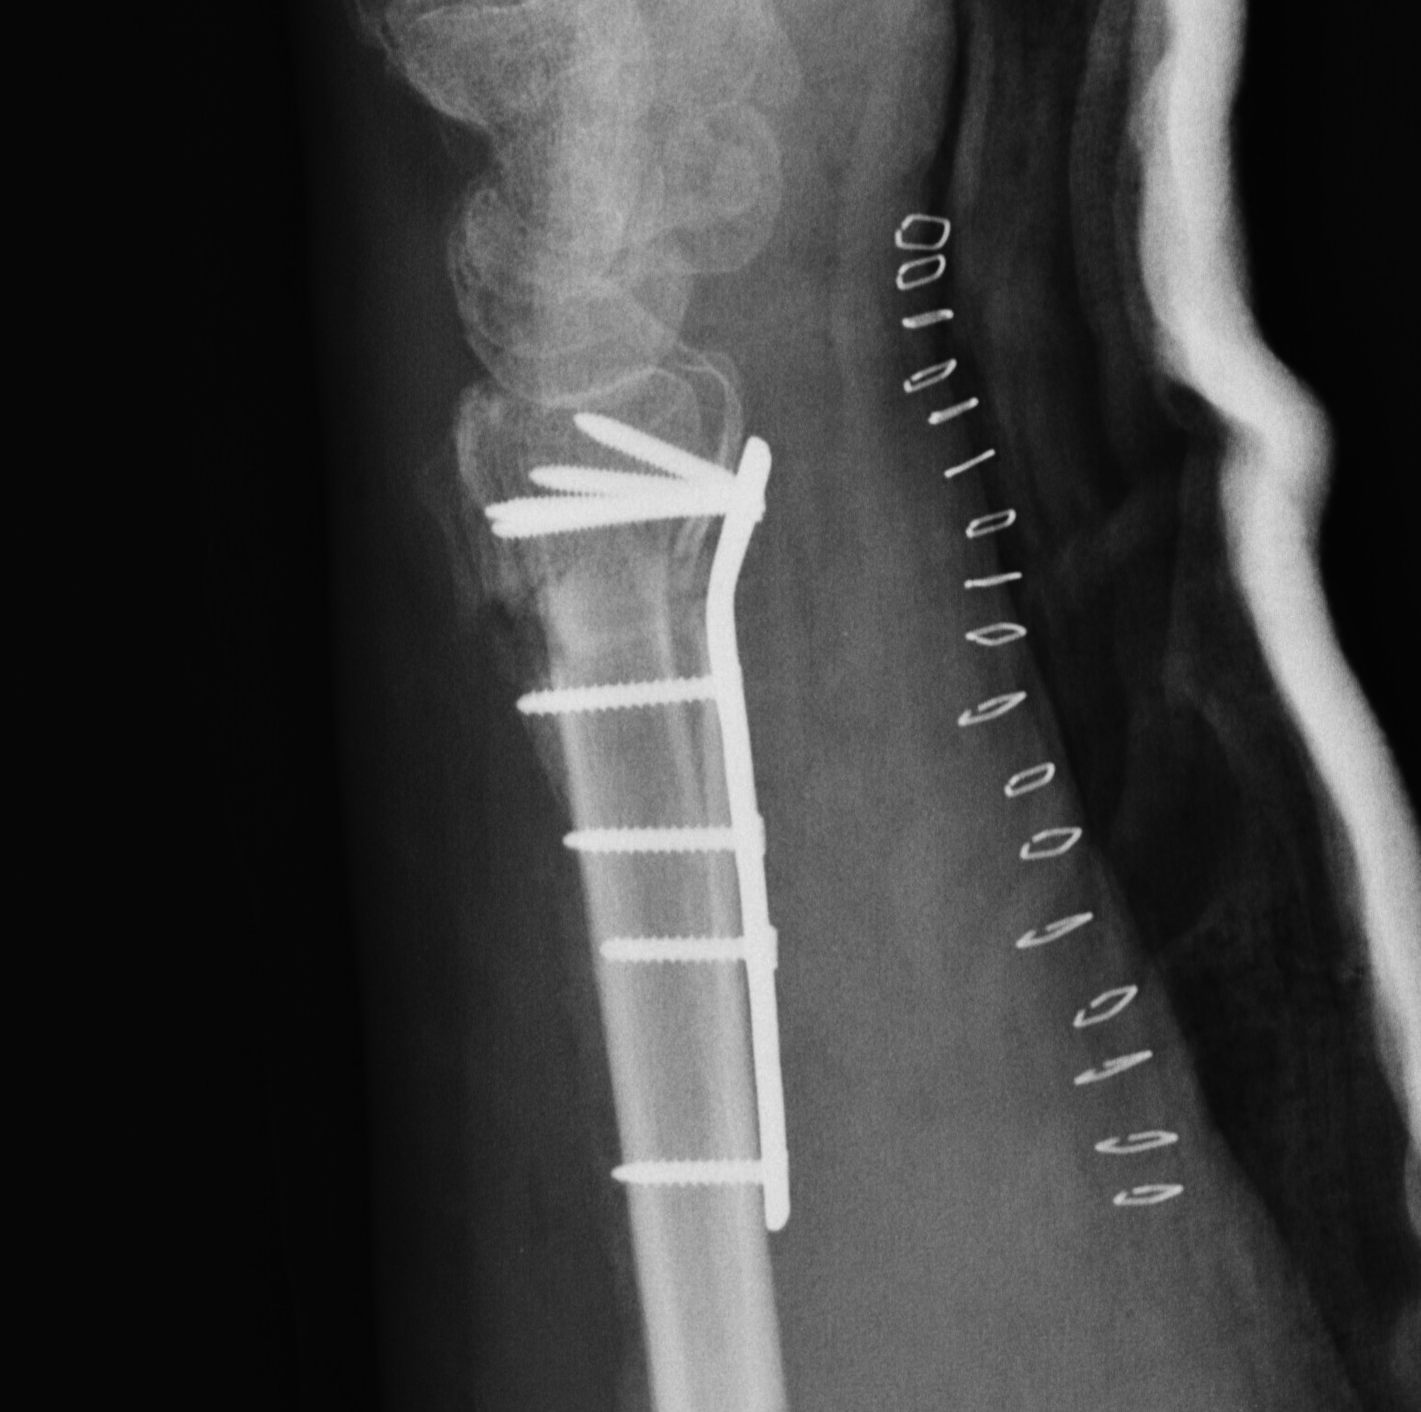

Dorsal opening wedge osteotomy

Distal Radial Malunion Dorsal OsteotomyDistal Radial Malunion Dorsal Osteotomy

Advantage

Lengthens the distal radius

May be easier to correct in coronal and sagittal plane

Disadvantage

Dorsal approach / dorsal plate - extensor tendon issues

Technique

3 / 4 dorsal approach

- expose distal radius

- can use half pins to control distal fragment

- protect structures with homan retractors

- osteotomy with microsagittal saw

- correct radial articular surface in sagittal & coronal planes

- trapezoidal bi-cortical iliac crest autograft / synthetic graft

- dorsal locking plate